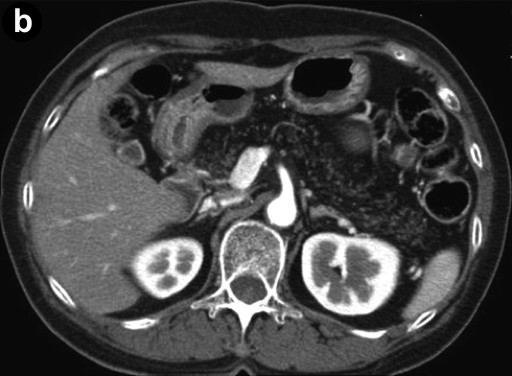

An esophagogastroduodenoscopy showed normal findings. Diseases such as reflux esophagitis and gastric ulcer were not observed. Ultrasonography (Figure 1) revealed a markedly heterogeneous pancreatic parenchyma demarcated from the neighboring tissues. The main pancreatic duct was not narrowed or dilated, and no tumor was detected. A CT image is shown in Figure 2. Plain CT (Figure 2a) revealed that the density of the pancreatic parenchyma had uniformly decreased to the same level as that of the surrounding fatty tissue. Contrast-enhanced CT (Figure 2b) revealed that the entire pancreatic parenchyma was absent and only a contrast-enhancing net-like shadow was visible. The magnetic resonance imaging (MRI) image is shown in Figure 3. The T1-weighted image could confirm that the entire pancreas was completely absent on T1-weighted images (fat suppression) (Figure 3). Endoscopic retrograde cholangiopancreatography (ERCP; Figure 4) showed no anomalous arrangement of the pancreaticobiliary ducts or pancreatic duct anomaly. Furthermore, obstruction, narrowing or dilatation of the main pancreatic duct was not observed. The branches of the pancreatic ducts appeared normal on the ERCP image. No abnormalities were observed in the bile duct.

Figure 2. Computed tomography. a. Plain: the density of the pancreatic parenchyma is uniformly decreased to the same level as that of the surrounding fatty tissue. b. Contrast-enhanced: the entire pancreatic parenchyma is absent and only a contrast-enhancing net-like shadow is observed. |